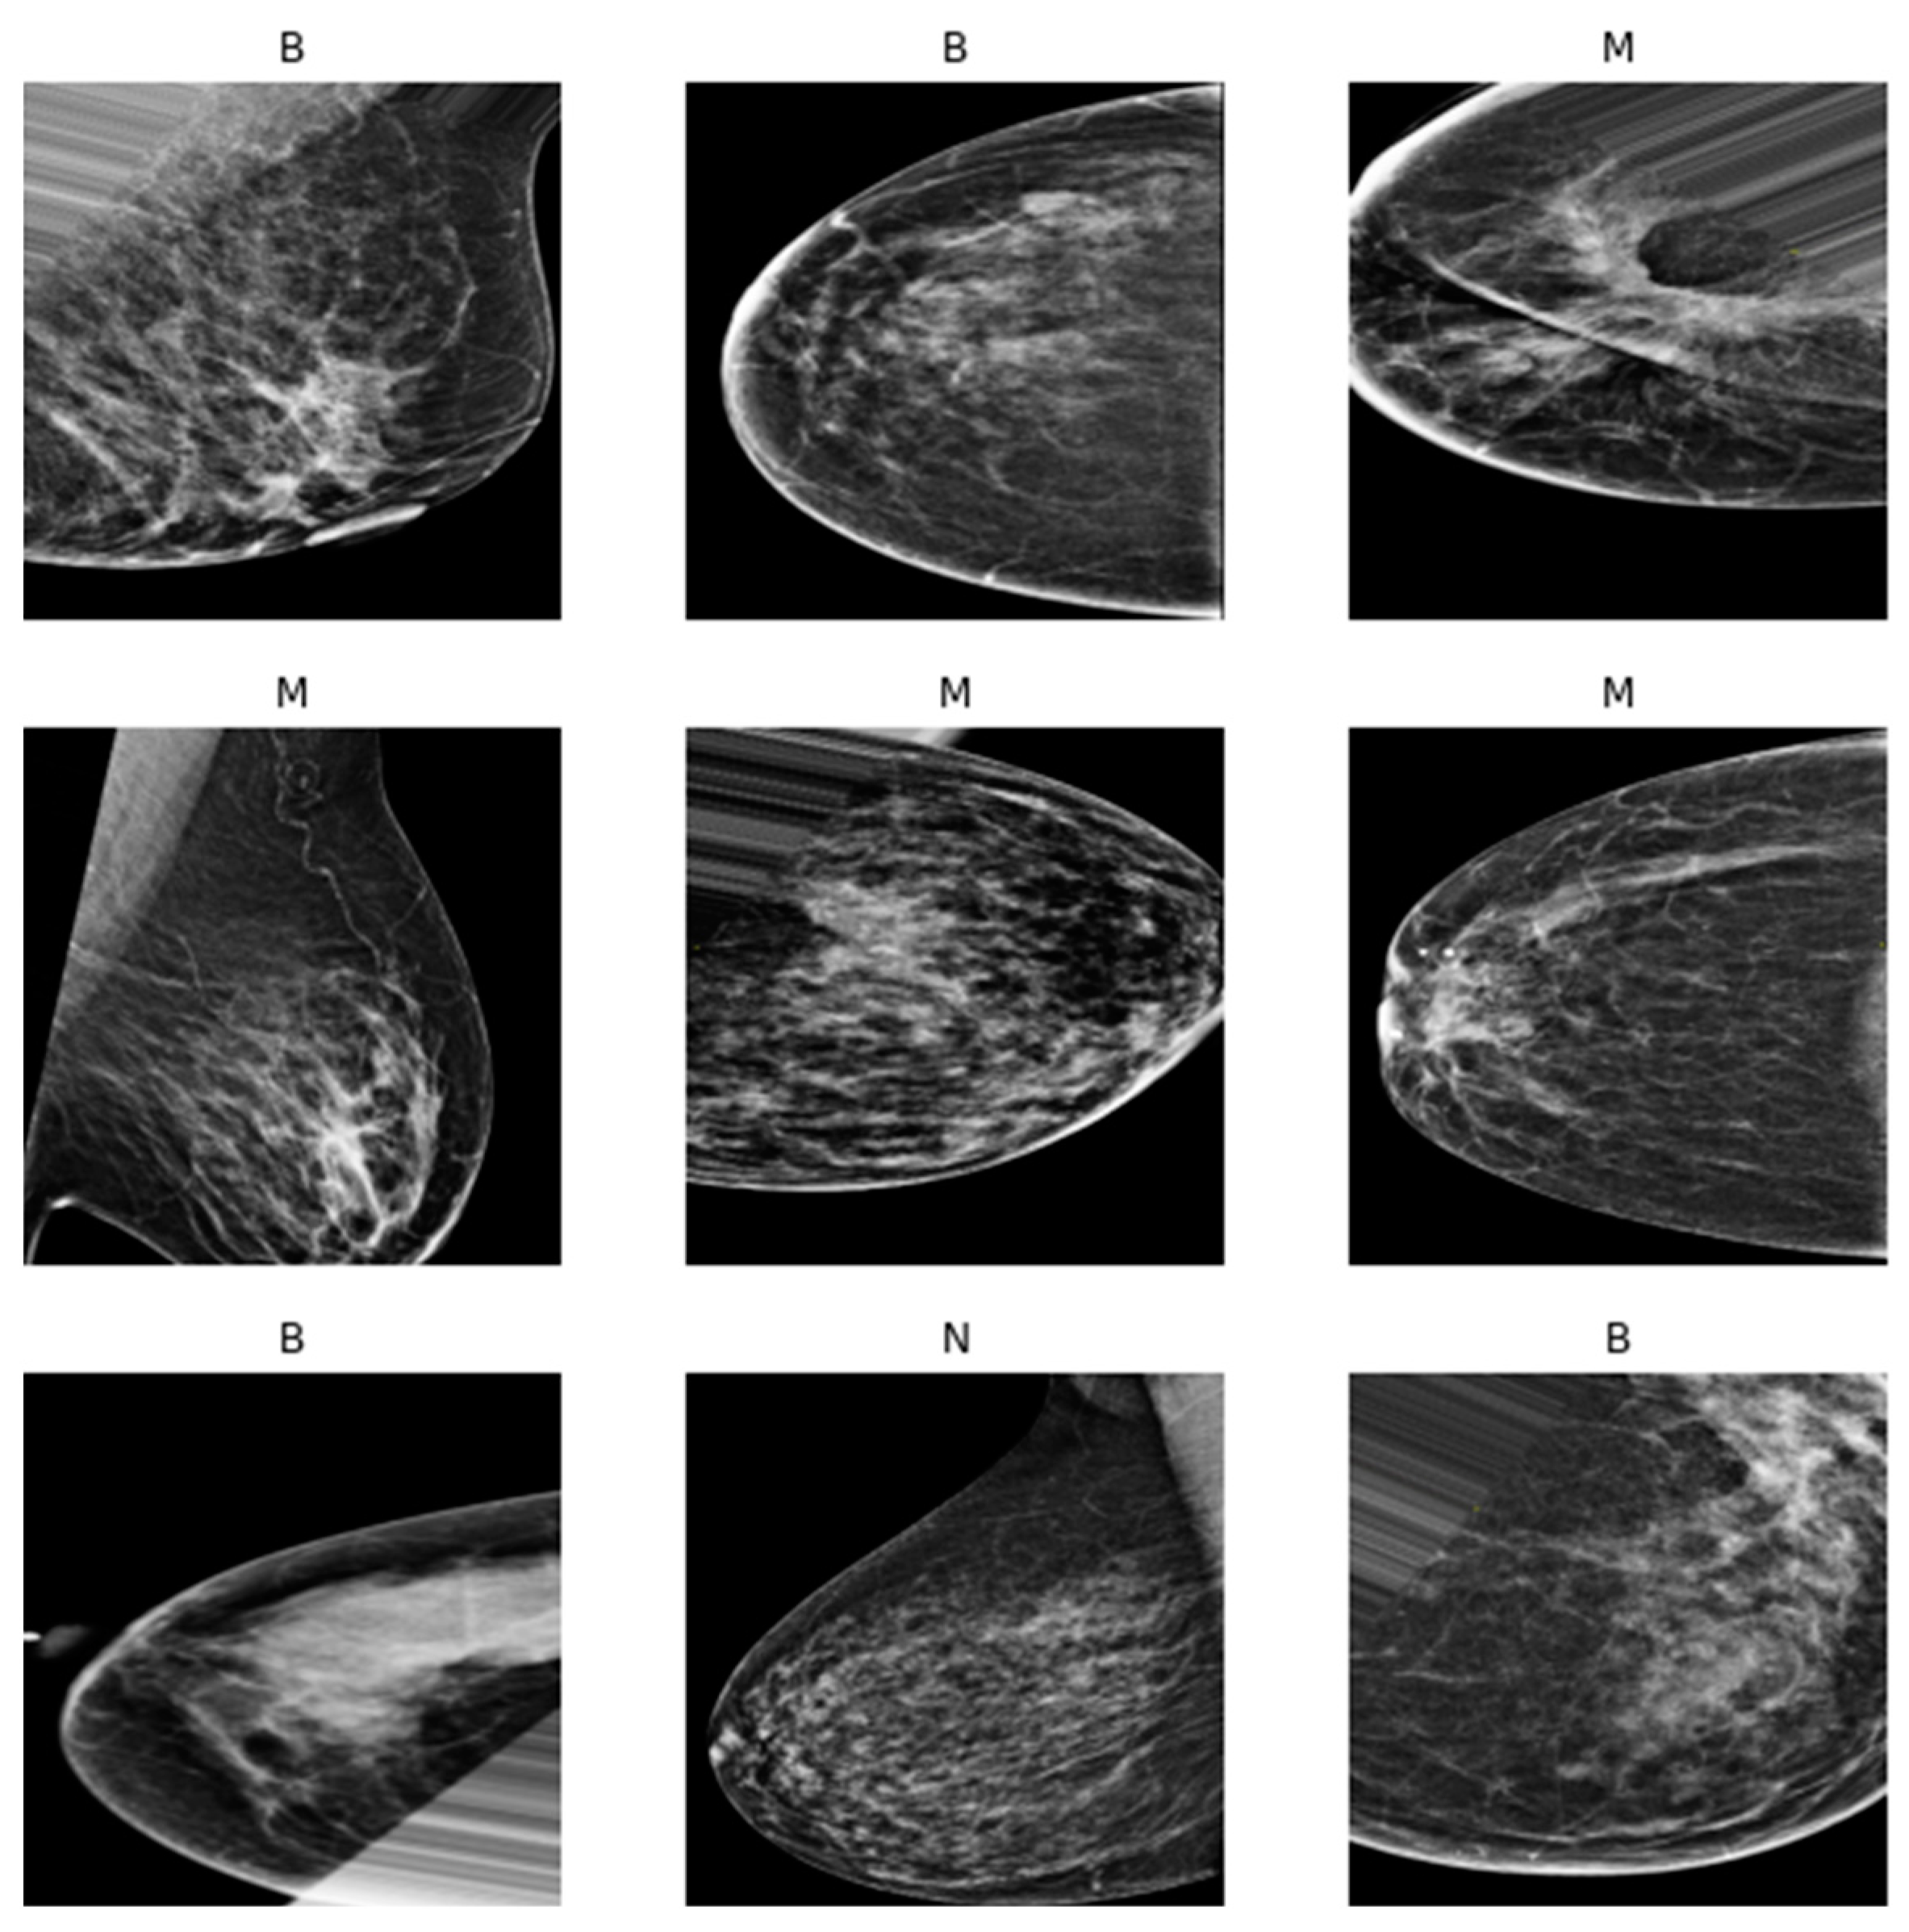

3.1. Dataset Descriptions

3.2. Mammogram Classification Using Deep Learning

3.4.1. First Experiment

3.4.2. Second Experiment

3.4.3. Third Experiment

| Experiment | Benign | Malignant | Normal |

|---|---|---|---|

| Experiment 1 | 192 | 268 | 0 |

| Experiment 2 | 40 | 236 | 360 |

| Experiment 3 | 360 | 236 | 1044 |

| Experiment 3 Balance Dataset | 236 | 236 | 236 |